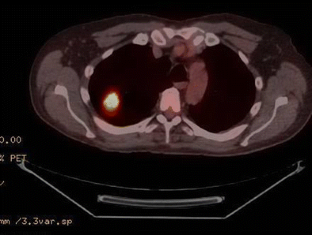

Fig. 3